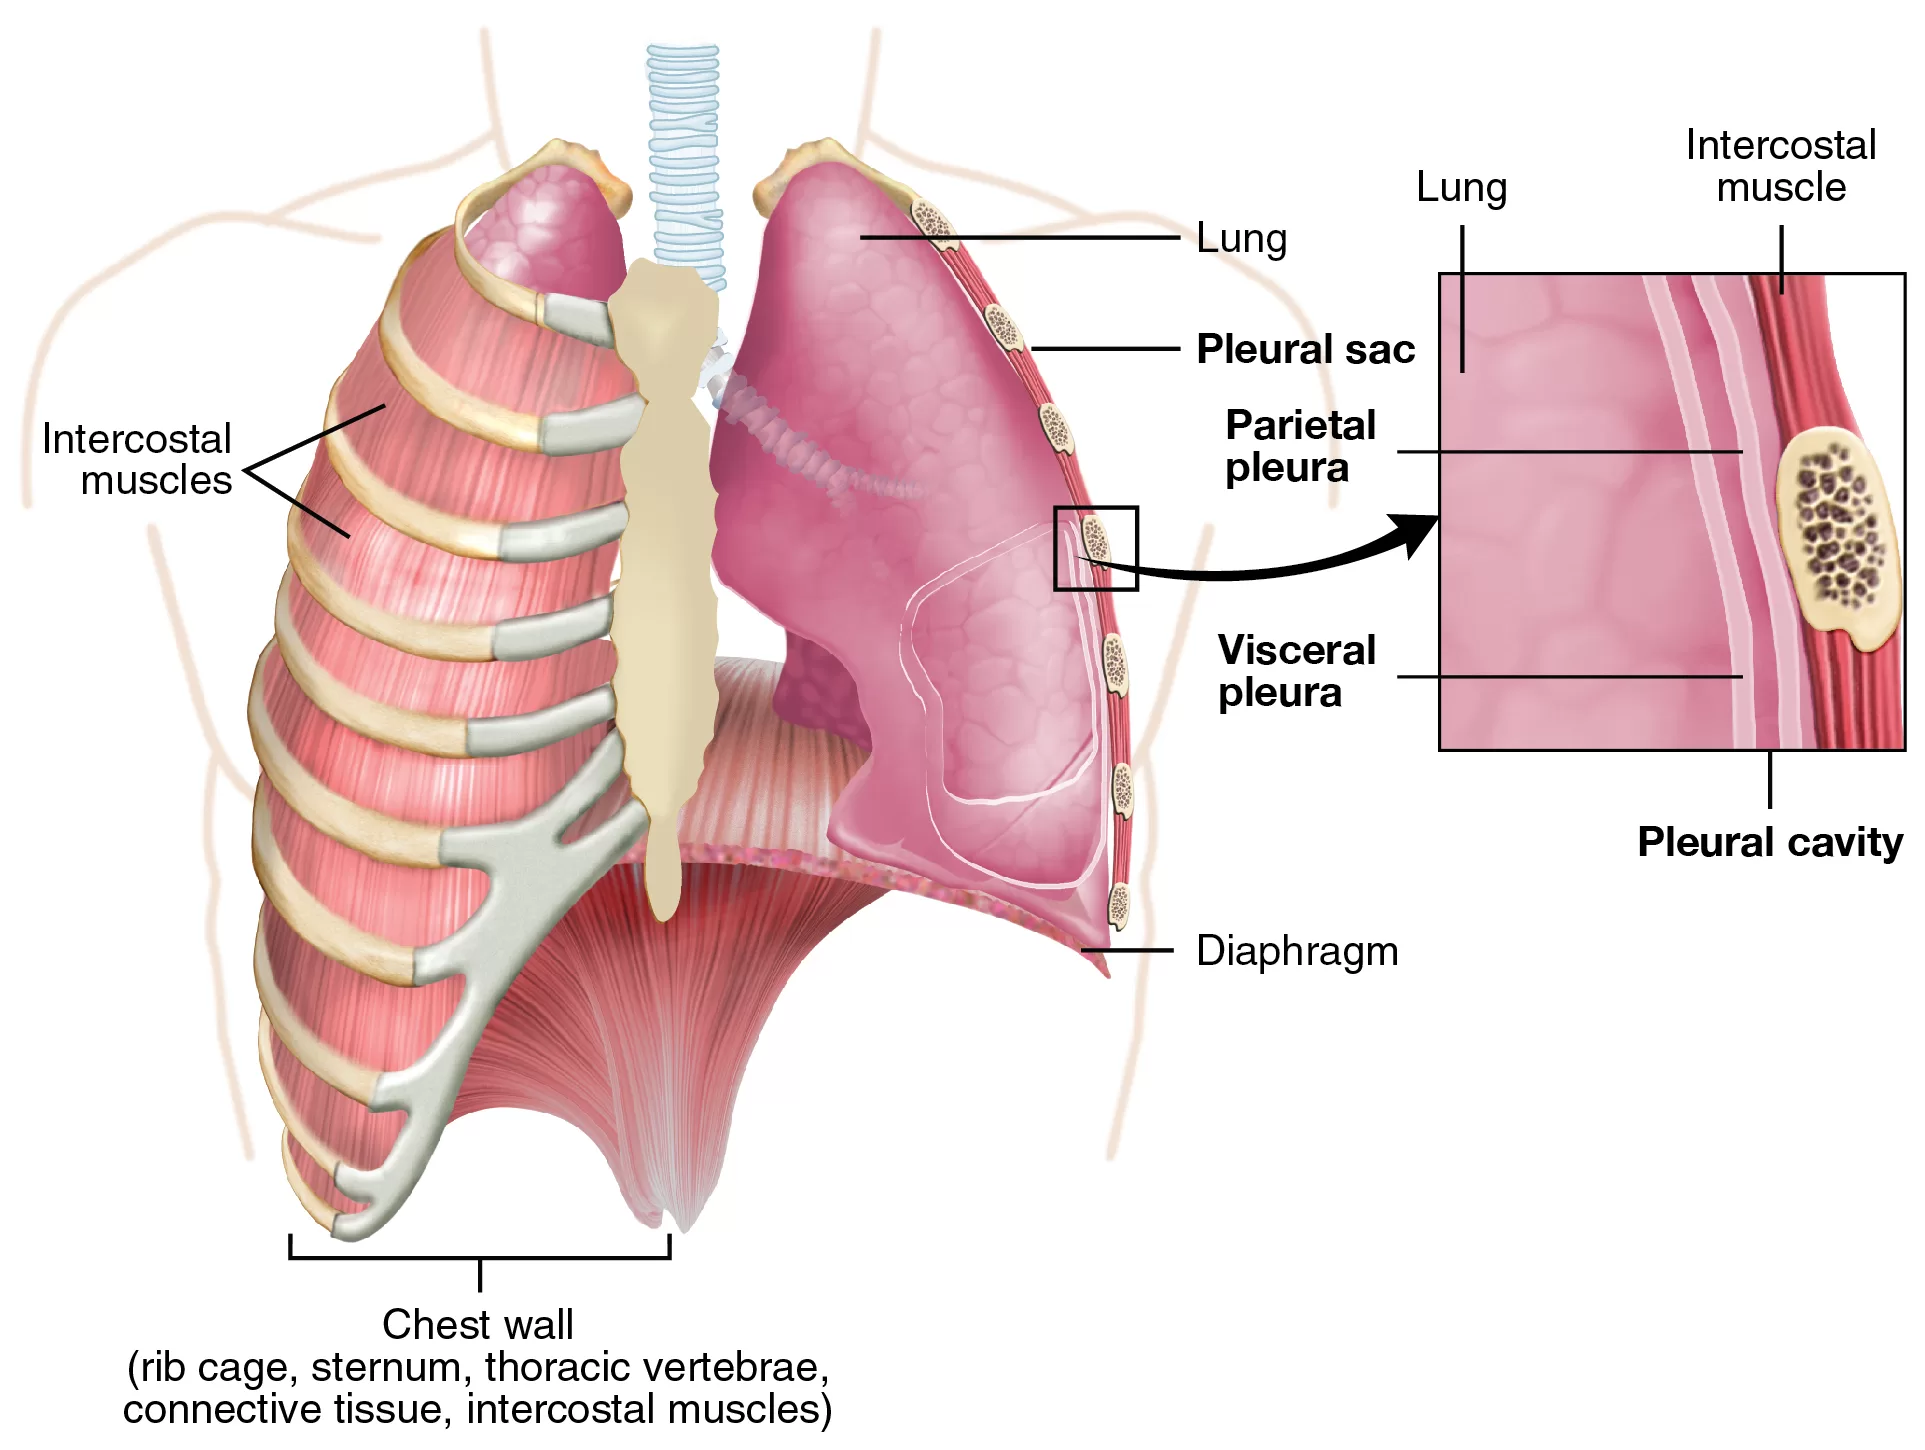

Paru-paru terletak di rongga dada tepat di atas sekiat diafragma. Diafragma adalah sekat rongga badan yang membatasi rongga dada dan rongga perut. Paru-paru terdiri dari dua bagian.

Paru-paru kanan memiliki tiga lobus, sehingga lebih besar dari paru-paru kiri yang terdiri dari dua lobus. Paru-paru dibungkus oleh dua lapis selaput paru-paru atau pleura. Di bagian dalam paru-paru terdapat gelembung halus yang merupakan perluasan permukaan paru-paru yang disebut alveolus, dan jumlahnya ± 300 juta buah. Luas permukaan alveolus diperkirakan mencapai 160 m² atau 100 kali lebih luas daripada luas permukaan tubuh.

8. Pleura

Pleura merupakan selaput pembungkus paru-paru terdiri atas:

- Pleura viscerale: melekat pada paru-paru, selaput bagian dalam yang langsung menyelaputi paru-paru disebut pleura dalam.

- Pleura parietale: melapisi dinding dada

- Pleura costalis: melapisi iga-iga, berupa selaput yang menyeliputi rongga dada yang bersebelahan dengan tulang rusuk disebut pleura luar.

- Pleura diafragmatika: melapisi diafragma

- Pleura servicalis: terletak di leher.

Antara selaput luar dan selaput dalam terdapat rongga berisi cairan pleura yang berfungsi sebagai pelumas paru-paru. Cairan pleura berasal dari plasma darah yang masuk secara eksudasi. Dinding rongga pleura bersifat permeabel terhadap air dan zat-zat lain.